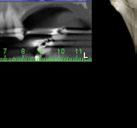

Este caso clínico es un premolar que tiene 3 conductos: sabemos que 2 de ellos son en la raíz vestibular, y

en el CBCT podemos apreciar a qué longitud del conducto se produce la bifurcación (Figura 10)

Debido a la gran curvatura que se produce en la bifurcación, tenemos que precurvar los instrumentos manuales y rotatorios, para facilitar que los instrumentos alcancen la LT (Figura 11). Terminamos el conducto mesiovestibular y palatino en conicidad .06 y el disto-vestibular en .04 debido al riesgo que pensamos que correríamos si hacemos una secuencia más amplia.

Valorando cada uno de los factores que hemos descrito anteriormente, podemos decidir, para el éxito de este tratamiento, una combinación: secuencia más progresiva; trabajar 3 ciclos por conducto para los instrumentos de preinstrumentación y conformación; eliminación de interferencias coronales con puntas ultrasónicas

e instrumento 25.09; terminar en conicidad .04/.06 según la dificultad del conducto; combinar movimiento continuo y alterno; y usar instrumentos precurvados de manera manual previo al rotatorio. Todo esto hará que resolvamos este caso clínico de manera satisfactoria (Figura 12). ●

Figura 10. Estudio Radiográfico en 2D y 3D del caso clínico. Figura 11. Secuencia operatoria que realizamos en cada uno de los conductos. Figura 12. Secuencia realizada para la obturación con onda continua.